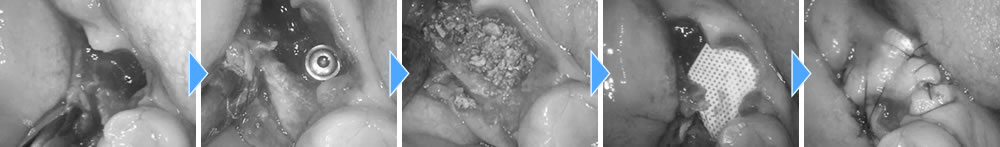

抜歯即時埋入インプラントの実施

まずは、根尖性歯周炎になっている右下の親知らずと手前の歯を抜歯しました。

親知らずの所は抜歯だけに留め、手前の歯の1本だけインプラントを埋入しました。膿がかなり大きくなってしまっており、骨が無くなってしまっていたため、骨造成も同時に行いました。